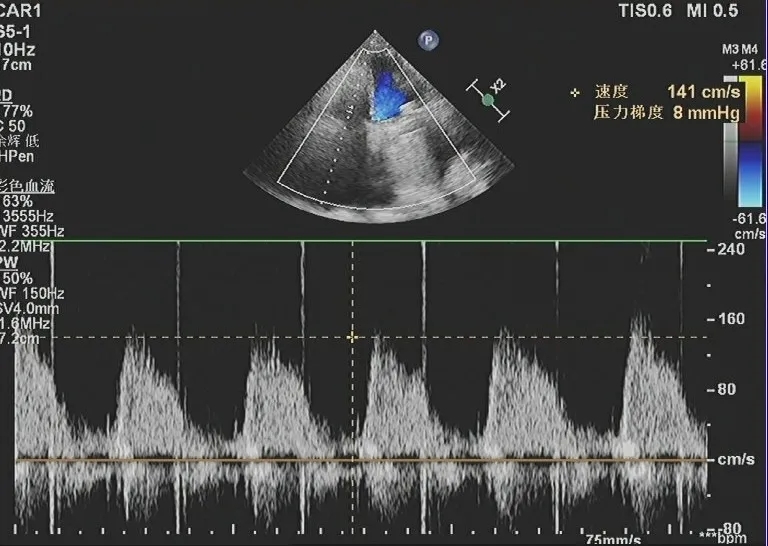

术后超声

患者三尖瓣生物瓣二次置换术后超声

三尖瓣位生物瓣置换术后,生物瓣功能良好。人工三尖瓣血流速度141cm/s,跨瓣压差8mmHg。